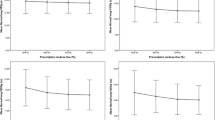

Figure 2 shows the DVHs for target volume and OARs in all 21 scenarios for SPArc and RO-IMPT plans for patient 6. Both plans could achieve an adequate coverage of at least 95% of ITV with the prescription dose under such uncertainties. Figure 3 shows the corresponding RVHs comparison for patient 6 (Fig. 3a) and the average mean AUC index of the fourteen cases and the corresponding p values (Fig. 3b). The average AUC index of the ITV, were very similar, with the corresponding average AUC values of 0.87 and 0.84 Gy (RBE) (p = 0.27) respectively for both plans. SPArc could significantly reduce the average AUC values from 1.55 Gy (RBE) to 1.39 Gy (RBE) (p = 0.002), 1.28 Gy (RBE) to 1.02 Gy (RBE) (p = 0.04), 1.20 Gy (RBE) to 1.05 Gy (RBE) (p = 0.004), 2.50 Gy (RBE) to 2.22 Gy (RBE) (p = 0.003), 0.89 Gy (RBE) to 0.81 Gy (RBE) (p = 0.002) for total normal lung, spinal cord, heart, esophagus, and integral body dose respectively.